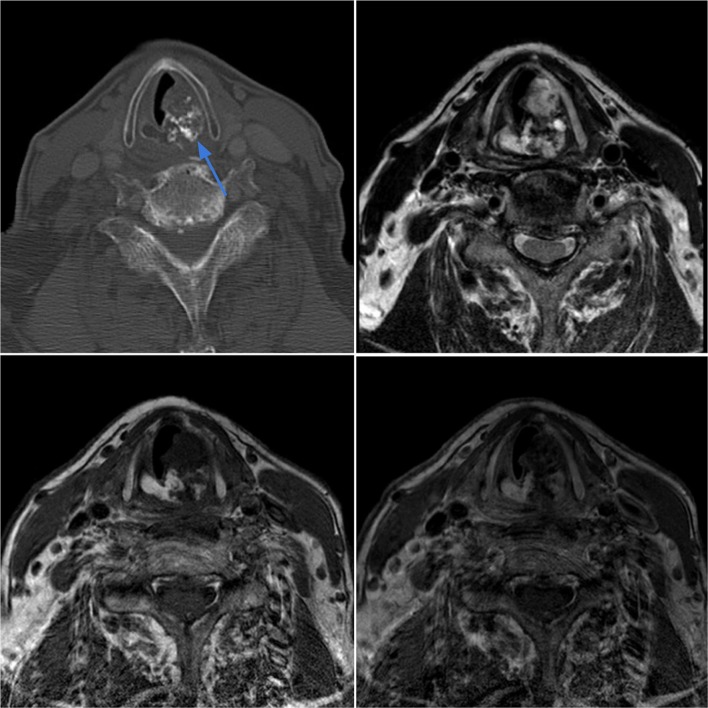

Case 3.

Ewing sarcoma of the left nasopharynx in a 3-year-old female with left ear pain and a visible oropharyngeal mass. Axial contrast-enhanced CT (top left) shows an infiltrative soft tissue mass in the left nasopharynx which displaces the nasal septum and invades the nasal cavity floor and roof of the soft palate. The lesion demonstrates intermediate T2 signal intensity (top right) with heterogeneous contrast enhancement on T1-weighted sequences (bottom images)